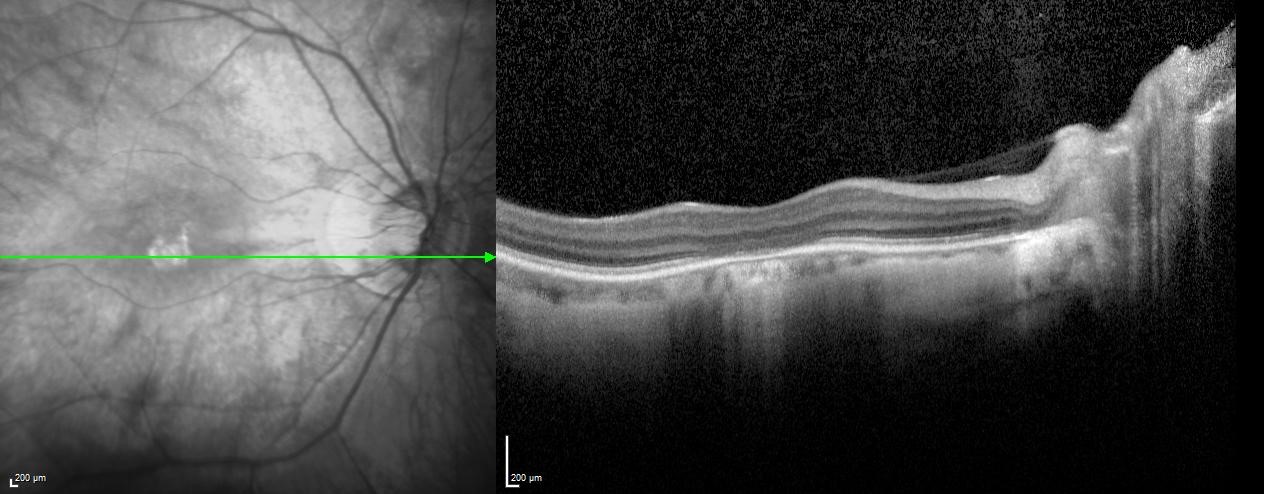

Optical coherence tomography (OCT) can provide diagnostic assistance as well as insight into the structure of dysfunctional cone cells. A hyporeflective “optical gap” can be found at the fovea that corresponds to foveal loss of photoreceptor outer segments. This finding is not specific to achromatopsia and can be seen in other retinal degenerations such as Stargardt’s disease, occult macular dystrophy and cone dystrophies.[13] Eventually the hyporeflective area involutes as seen in Figure 1. The disease has been described to go through sequential stages that can be followed on OCT (Table 1).[14] However, a functional decline association with this proposed sequence has not been found.[15][16] The cones may be nonfunctional at birth but still physically present - degradation over time may result in these structural changes without a corresponding change in function. The OCT stages may also not be sequential for all patients and could represent the end-stages of different degrees of cone dysfunction.

Table 1. OCT stages of Achromatopsia

| Stage | Description |

|---|---|

| 1 | Intact outer retina |

| 2 | Ellipsoid zone disruption |

| 3 | Optically empty space |

| 4 | Optically empty space with partial retinal pigment epithelium disruption |

| 5 | Outer nuclear layer loss and/or complete retinal pigment epithelial disruption |